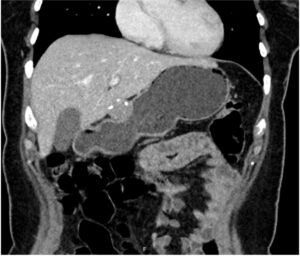

Contrast-enhanced computed tomography revealed a well-defined, 30 × 30mm nodular lesion with dense internal calcification arising from the gastric antrum wall, without unequivocal arterial phase contrast enhancement (Figure 2).

Figure 2: Contrast-enhanced CT scan showing a gastric wall nodular lesion with peripheral calcifications.